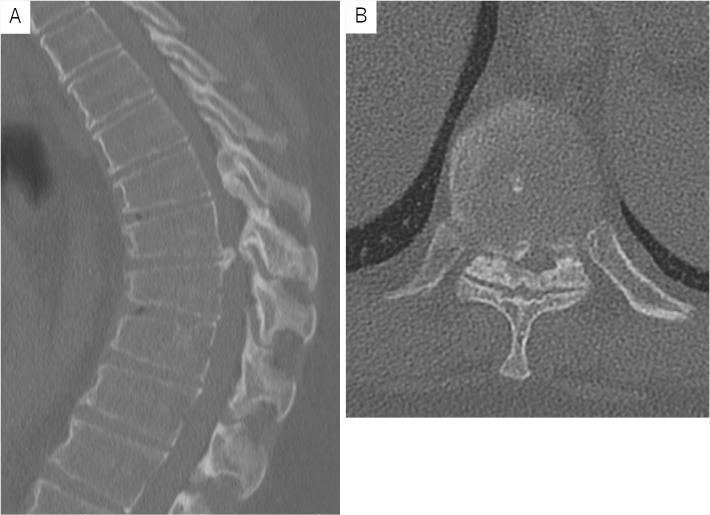

Thoracic Myelopathy with Scheuermann's Disease and Ossification of the Yellow Ligament: A Case Report.